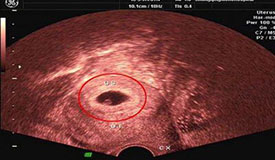

腹部彩超